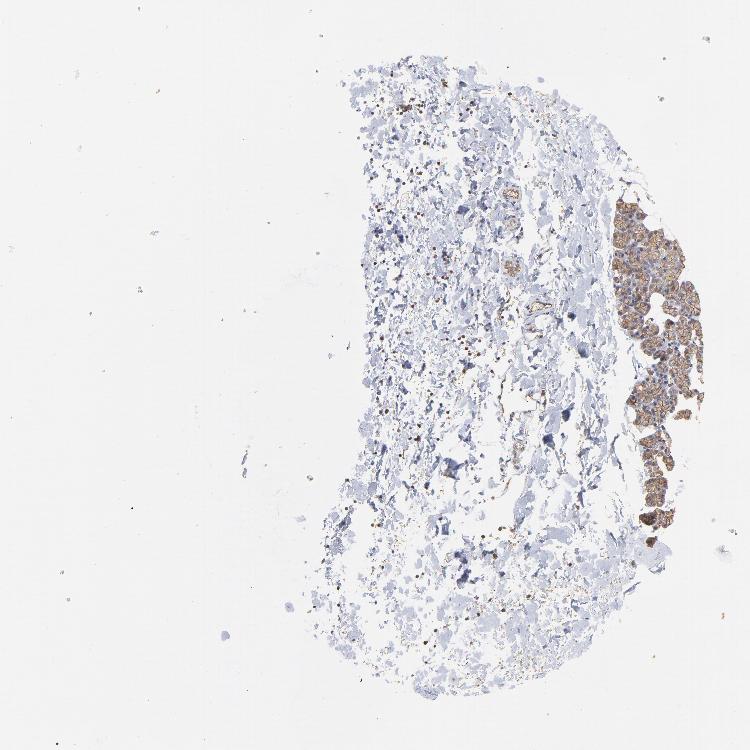

SALIVARY GLAND - Antibody stainingi

Antibody staining in the annotated cell types in the current human tissue is reported as not detected, low, medium, or high, based on conventional immunohistochemistry profiling in selected tissues. This score is based on the combination of the staining intensity and fraction of stained cells.

Each image is clickable and will lead to virtual microscopy that enables deeper exploration of all samples and also displays staining intensity scores, fraction scores and subcellular localization as well as patient and tissue information for each sample.

Antibody HPA003004Antibody HPA005819

Glandular cells MediumNot detected